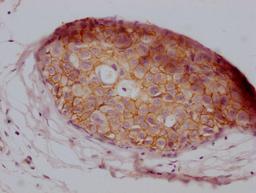

IHC image of CSB-MA907551 diluted at 1:100 and staining in paraffin-embedded human breast cancer performed on a Leica BondTM system. After dewaxing and hydration, antigen retrieval was mediated by high pressure in a citrate buffer (pH 6.0). Section was blocked with 10% normal goat serum 30min at RT. Then primary antibody (1% BSA) was incubated at 4°C overnight. The primary is detected by a Goat anti-mouse IgG polymer labeled by HRP and visualized using 0.05% DAB.